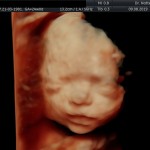

Modalidad de imagen ecográfica que permite evaluar, medir y capturar estructuras fetales superficiales e internas en 3 dimensiones (3D) y también en movimiento y en tiempo real (4D) con programas de realismo aumentado (HD LIVE) e imágenes tomografías fetales (TUI) mejorando significativamente la precisión en las mediciones fetales y la documentaciones de estructuras anatómicas.

Esta tecnología se puede utilizar desde la 6ta a la 40ma semana de embarazo.